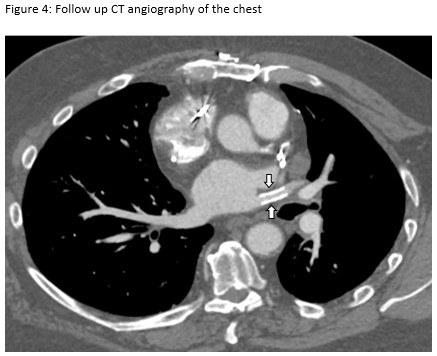

A 72-year-old man presented for evaluation of progressive dyspnea with concern for interstitial lung disease (ILD). He had an extensive cardiac history with prior cardiac bypass surgery and atrial appendage exclusion, followed by multiple subsequent radiofrequency ablations targeting arrhythmogenic foci. His last ablation procedure was three years prior to presentation. He reported reduced exertional tolerance, and was only able to ambulate a few blocks. As a part of his work-up, his local pulmonologist had obtained a high-resolution computed tomography (HRCT) of the chest, which showed abnormalities limited to the left upper lobe (Figure 1). He was treated with antibiotic therapy and corticosteroids but had no improvement so a surgical lung biopsy was performed. These images and biopsies were reviewed at our institution. A representative picture of histology from the biopsy is shown in Figure 2. After his visit to the ILD clinic, a CT angiogram of the chest was obtained and is shown in Figure 3.